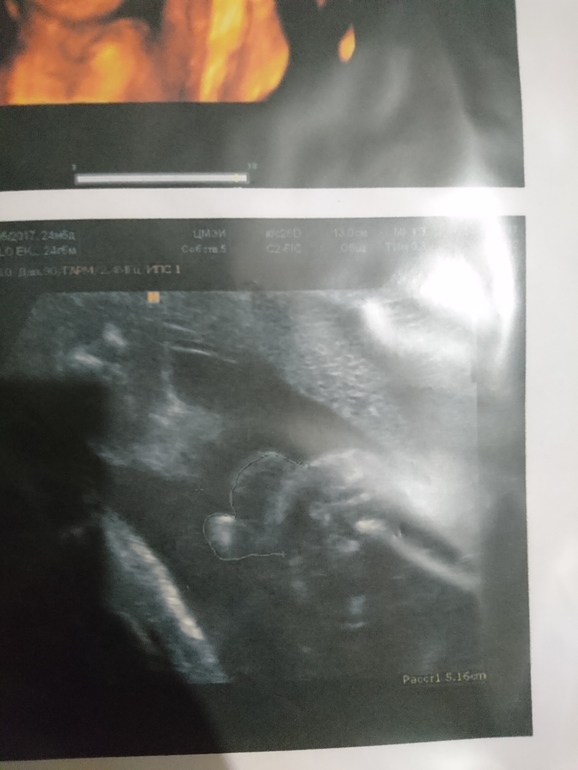

III скрининг, 32 неделя подходит к концу, жидкость в почках

На консультации в ЖК, выбор женской консультации/гинекологаНачнем с веселого! Третий скрининг позади, осталось совсем чуть-чуть ☺️. ИИИИ наша девочка отрастила ЯЙЦА! 🤣. Таким образом Алиса превратилась в Яна! Но это не точно...! 😁 хотя судя по фото.... как думаете? Врач сказала что это яички, но писюнчика так и не нашла.

Это ж надо. 3 узи за девочку, 3 за мальчика. Теперь точно как в сказке Пушкина... ждем не то сына, не то дочь 😄